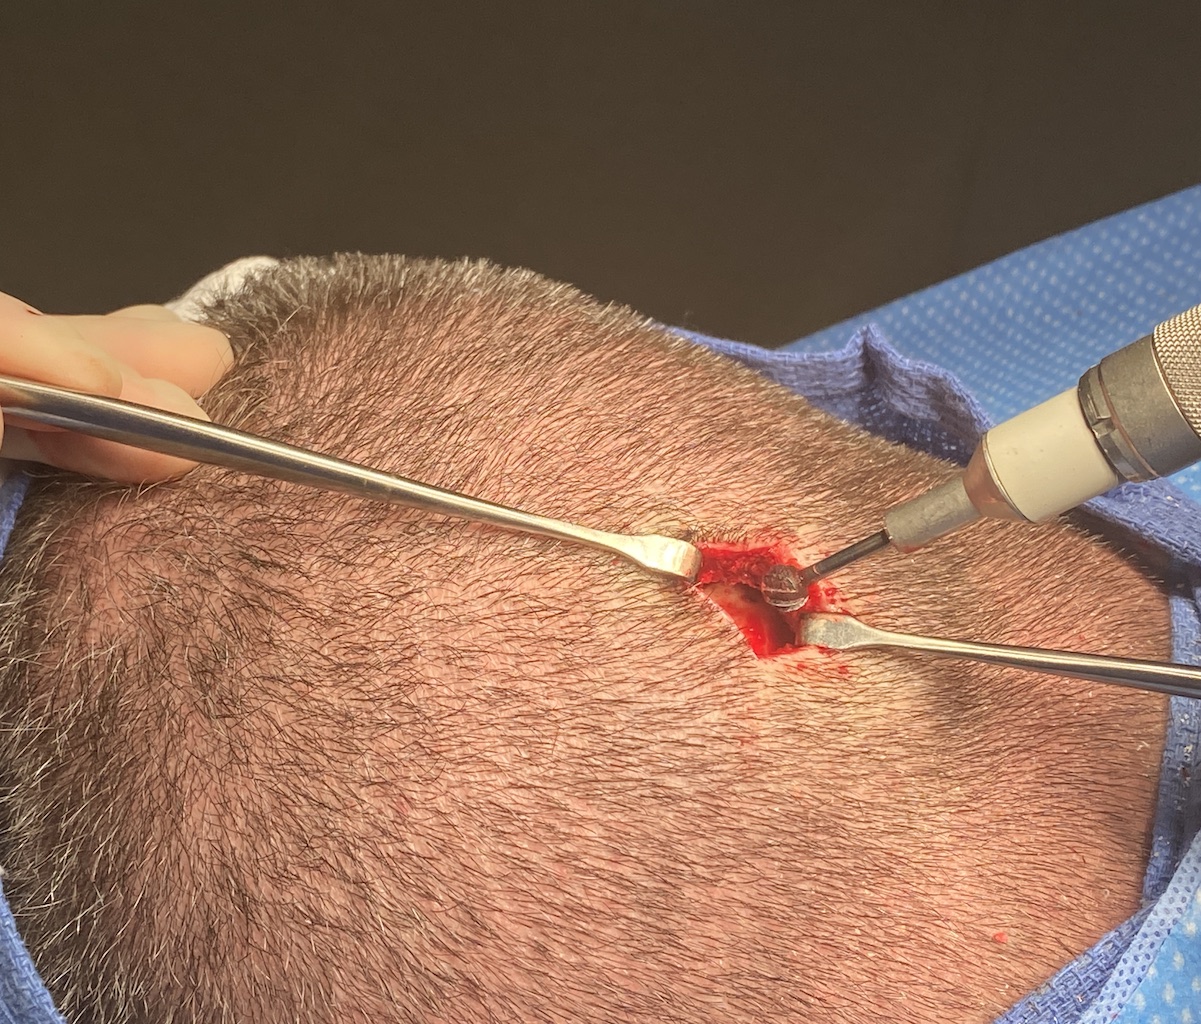

Desire for reduction of prominent occipital knob deformity.

Intraoperative result from occipital knob skull reduction through a direct small scalp incision.

Desire for reduction of prominent occipital knob deformity.

Intraoperative result from occipital knob skull reduction through a direct small scalp incision.